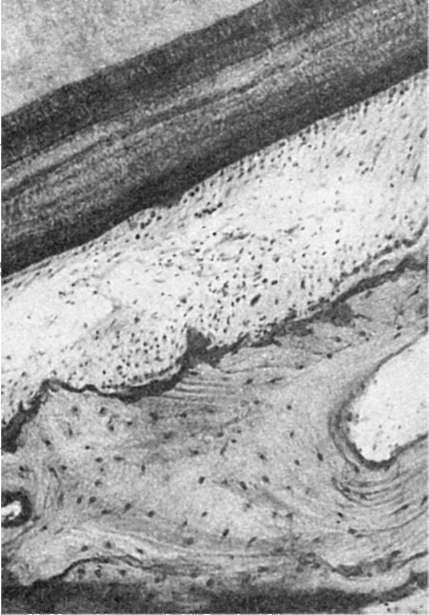

Рис. 355. Пародонтит. Патологический пародонтальный карман, выстланный многослойным плоским эпителием; клеточная воспалительная инфильтрация ткани пародонта

Пародонтальный карман заполнен бесструктурной массой, содержащей колонии микробов, остатки пищи, большое число разрушенных лейкоцитов. При обострениях заболевания глубина кармана увеличивается и по степени ее определяют степень пародонтита. Наружная стенка кармана и дно ее образованы грануляционной тканью, покрытой и пронизанной тяжами многослойного плоского эпителия (см. рис. 355). При этом эпителий достигает верхушки зуба. В грануляционной ткани много нейтрофилов, плазматических клеток, макрофагов и лимфоцитов. Из кармана, особенно в период обострений заболевания, выделяется гной (альвеолярная пиорея). Со временем в альвеолярных отростках челюстей развивается остеопороз, очень хорошо определяемый на рентгеновских снимках.